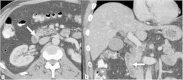

Malignancies of the biliary tract include cholangiocarcinoma, gallbladder cancers and carcinoma of the ampulla of Vater. Biliary tract adenocarcinomas are the second most common primary hepatobiliary cancer. Due to their slow growing nature, non-specific and late symptomatology, these malignancies are often diagnosed in advanced stages with poor prognosis. Apart from incidental discovery of gall bladder carcinoma upon cholecystectomy, early stage biliary tract cancers are now detected with computed tomography (CT) and magnetic resonance imaging (MRI) with magnetic resonance cholangiopancreatography (MRCP). Accurate characterization and staging of these indolent cancers will determine outcome as majority of the patients' are inoperable at the time of presentation. Ultrasound is useful for initial evaluation of the biliary tract and gallbladder masses and in determining the next suitable modality for further evaluation. Multimodality imaging plays an integral role in the management of the biliary tract malignancies. The imaging techniques most useful are MRI with MRCP, endoscopic retrograde cholangiopancreatography (ERCP), endoscopic ultrasound (EUS) and positron emission tomography (PET). In this review we will discuss epidemiology and the role of imaging in detection, characterization and management of the biliary tract malignancies under the three broad categories of cholangiocarcinomas (intra- and extrahepatic), gallbladder cancers and ampullary carcinomas.